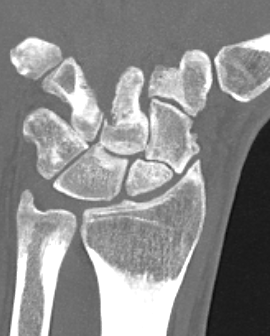

Scaphoid non union advanced collapse

Nonunion with resultant radiocarpal and midcarpal OA

Pathology

Scaphoid nonunion

- flexion deformity and abnormal joint mechanics

- radiocarpal osteoarthritis

- progresses from radial styloid / scaphoid fossa / midcarpal joint

- radiolunate joint preserved

Vender Classification

| Stage I | Stage II | Stage III |

|---|---|---|

|

Radial styloid and distal scaphoid fragment

+ Proximal scaphoid and capitate | + capitate-lunate joint |